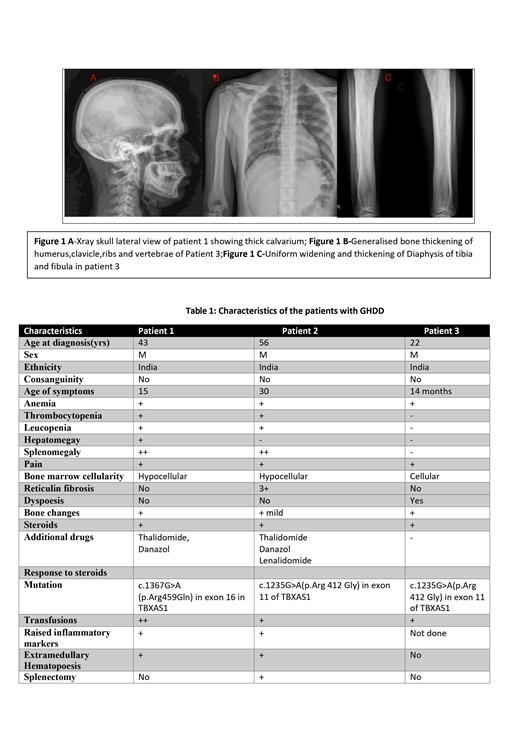

The first patient, a 43-year-old male, had a history of anemia since childhood and became transfusion dependent after 15 years of age. He developed bicytopenia and later pancytopenia with hypocellular bone marrow , along with splenohepatomegaly and extramedullary hematopoiesis in the paravertebral and presacral areas, a novel finding in GHDD cases. Whole exome sequencing revealed a missense mutation in the TBXA2 gene.

The second patient, a 56-year-old male, had a history of anemia since childhood and underwent splenectomy at 46 due to massive splenomegaly and transfusion dependency. However, his transfusion dependency persisted, and bone marrow biopsy suggested myelofibrosis. However he was negativefor myeloid mutations including JAK2. Subsequently, genetic testing revealed a homozygous missense mutation in the TBXAS1 gene. He also developed paraplegia and bladder incontinence, attributed to extramedullary hematopoiesis, which improved with steroid treatment

The third patient a 23 year old man with history of anemia, lower limb tenderness and ecchymosis at 14 months of age. Evaluation then had shown hyperostosis of diaphysis of long bones of lower limbs with sparing of metaphysis and bicytopenia. Was on regular transfusions till 9 years. Re-evaluation with bone marrow studies at 9 years revealed a varying cellular marrow with dysplastic megakaryocytes and diagnosed as pediatric myelodysplatic syndrome ,He was on steroids till 13 years and he did not require further transfusions.He stopped steroids for 1 year following which there was a fall in Hb levels and recurrence of pain in both lower limbs with inability to squat. In view of history of steroid responsive anemia and thickening of diaphysis in X-rays GHDD was suspected and confirmed by genetic testing. He was restarted on steroids and there was a good response to steroids within 4 week with normalisation of hemoglobin levels .